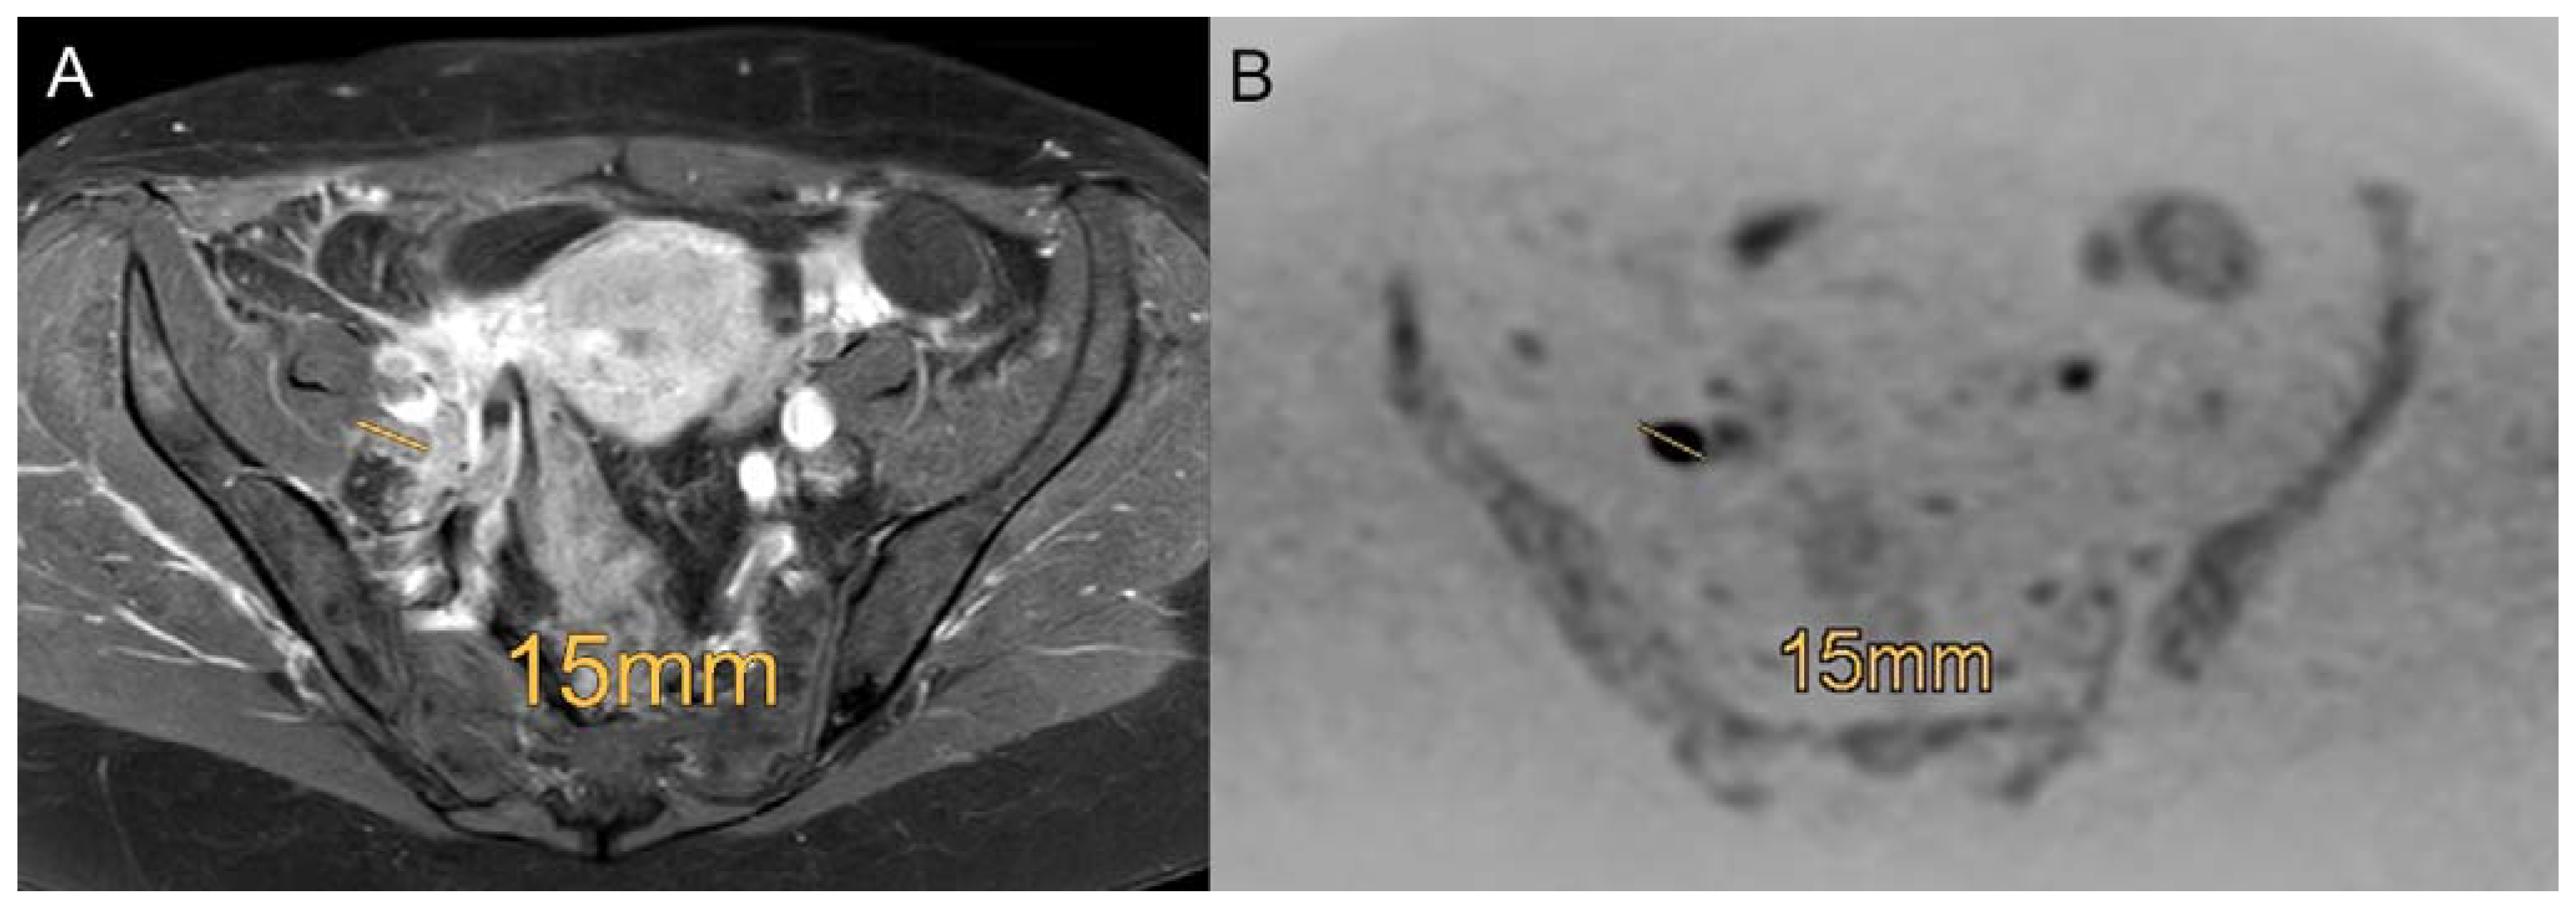

Figure 4. Example of a patient with a FIGO IIIC1 cervical carcinoma with involvement of pelvic lymph nodes using the standard MRI ((A), contrast enhanced transversal T1-weighted scans with fat saturation) and DWIBS (B) with a right-sided 15 mm lymph node metastasis proven by histopathology. Diagnosis is more reliable in DWIBS (B) compared to contrast enhanced transversal T1-weighted scans with fat saturation (A).